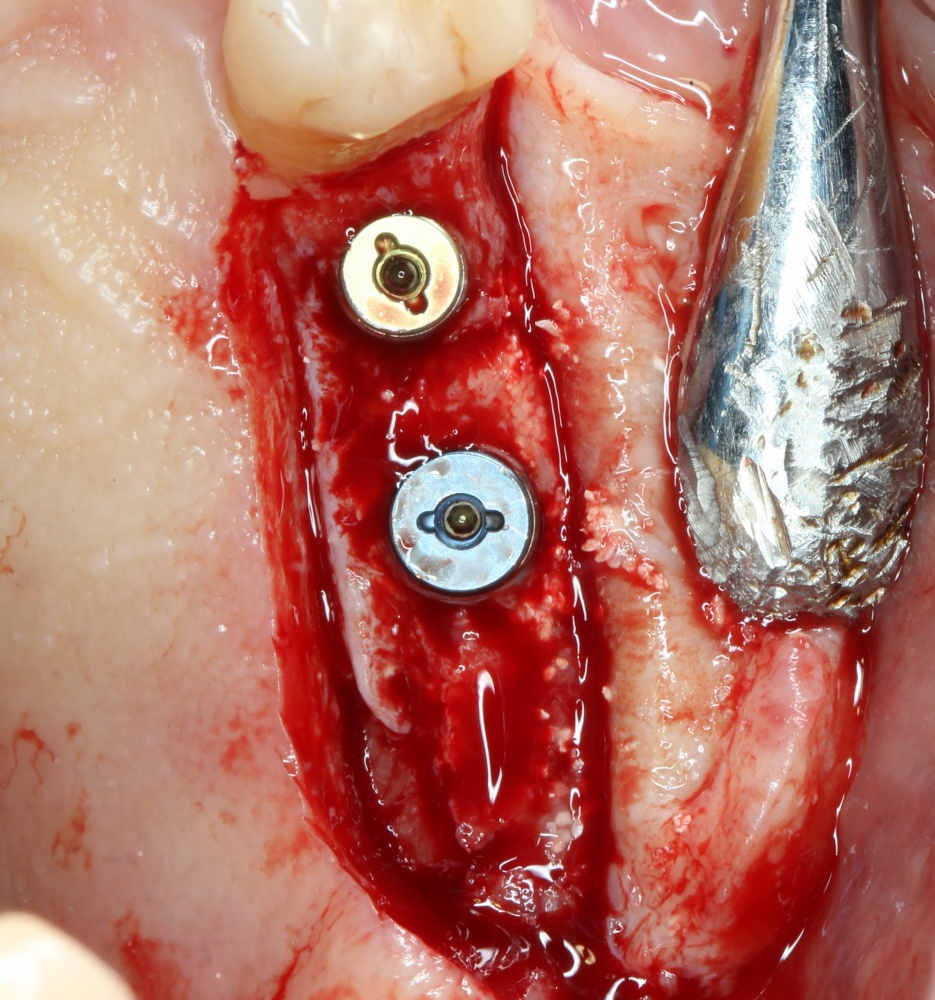

Я зафиксировал костный блок практически без адаптации на несколько винтов. Обрати внимание, что винты находятся в зоне, где не планируется установка имплантатов. Фиксация должна быть надежной, поскольку мне еще предстояла подготовка лунок для имплантатов. Трех винтов для этого вполне достаточно.

Напомню, что для этой работы я выбрал субкрестальные имплантаты Ankylos C/X. Они прекрасно сочетаются с любым методом остеопластики.

Я не планирую установку супраструктур или коронок, поэтому на уровень первичной стабильности можно положить болт. Даже наоборот — чем меньше крутящий момент при установке, тем лучше. Для имплантатов Ankylos и подобных им, это особенно важно. В общем, момент силы при установке — не более 10-15 Нсм.

Ремарка: имплантаты с предустановленными имплантодержателями хороши тем, что с ними легко контролировать позиционирование имплантатов. В случае с Ankylos С/Х - еще и крутящий момент. Имплантодержатель должен отсоединяться от имплантата с легким щелчком. Если его клинит, и тебе приходится прикладывать для этого усилия, то ты, однозначно, превысил момент силы во время установки имплантата. Следовательно, жди проблем.

Глянем на то, что получилось: